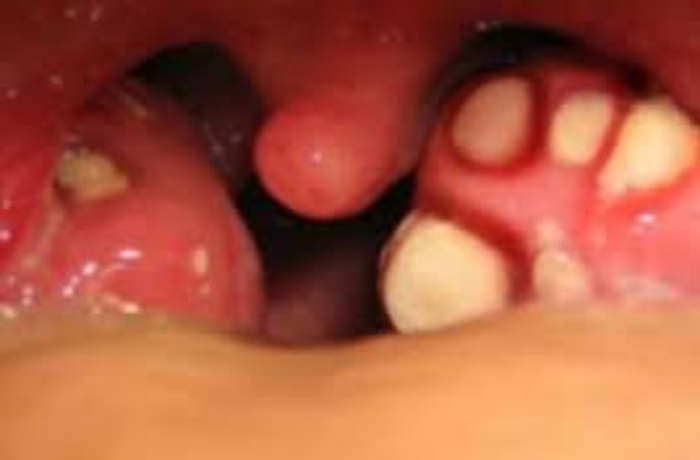

Infectious Mononucleosis, a common problem viral infection in adolescence spread by close contact.

Tonsillar crypts cause teenagers a great deal of angst, may contribute

to halitosis and can be severe enough to warrant tonsillectomy.